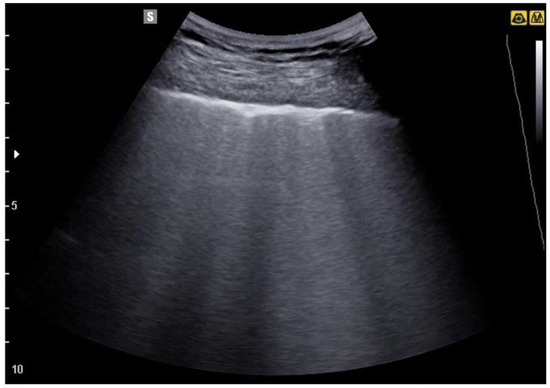

3. Lung Ultrasound Evaluation

4. Lung Ultrasound on Physiological Lung